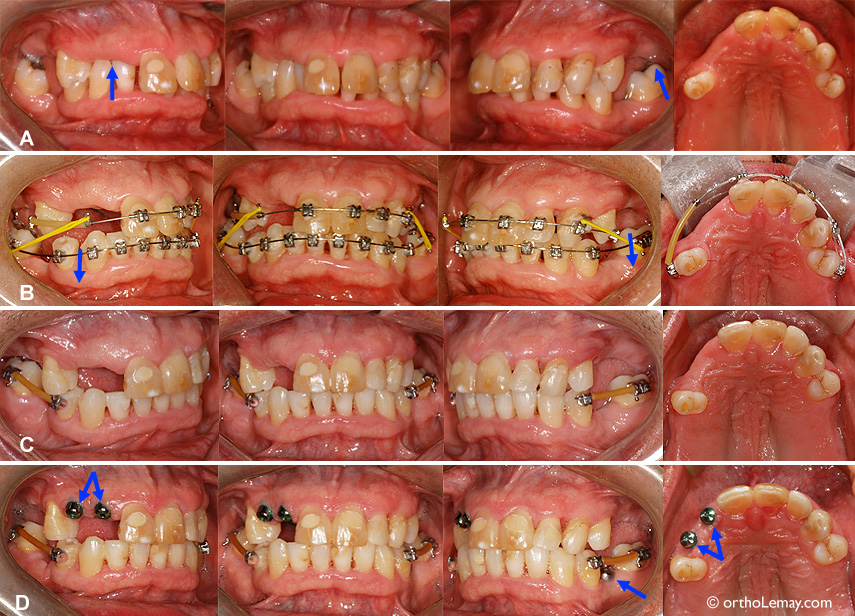

Exemple de l’intrusion orthodontique d’une dent qui s’était “allongée” (extrusion) avec les années à la suite de la perte d’une dent à l’arcade opposée. L’espace inter-arcade ne permet pas au dentiste de faire une prothèse inférieure adéquate à cause du manque d’espace.

(A) Prémolaire supérieure gauche “descendue” et espace minime avec l’arcade du bas (flèche jaune).

(B) Mécanique orthodontique utilisée pour “intruder” ou remonter la dent.

(C) Après l’intrusion de la dent.

(D) À la fin de l’orthodontie, l’espace disponible (flèche jaune) permet maintenant de fabriquer une prothèse inférieure.

Note : Ce patient de 57 ans avait une prothèse amovible supérieure qui remplaçait les 2 incisives centrales supérieures. La prothèse n’est pas en bouche sur la photo finale.